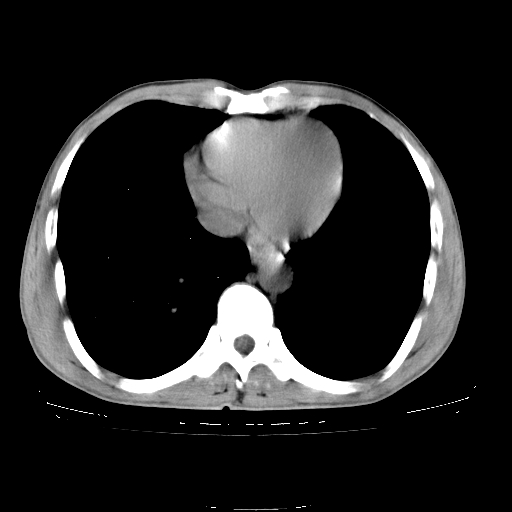

以下是引用yangyudong333在2008-4-29 5:38:00的发言:[br]比较典型的矽肺结节.支持[br]诊断依据:[br] 1.x线表现:[br] ①典型矽肺为多发直径 1~3mm 小结节,即矽结节,由胶原纤维和硅尘构成,可融合成团块,好发于上肺。[br] ②团块周围常有肺大泡。[br] ③胸内淋巴结增大、钙化。如肺门淋巴结呈蛋壳样钙化有助于与其他尘肺区别。[br] ④胸膜常广泛粘连、增厚。[br] 2.ct表现[br] ①两肺散在大小较为一致的小结节影,其密度较高,边界清楚。[br] ②小结节可融合为较大团块影,直径约 1cm ,甚至可达 10cm以上,易发生在上叶。[br] ③小结节周围常并有小叶中心气肿或弥漫性肺气肿。

以下是引用liuyue在2008-4-28 22:30:00的发言:[br]比较典型的矽肺结节.[br]请结合临床及化验除外矽肺合并肺结核之可能.